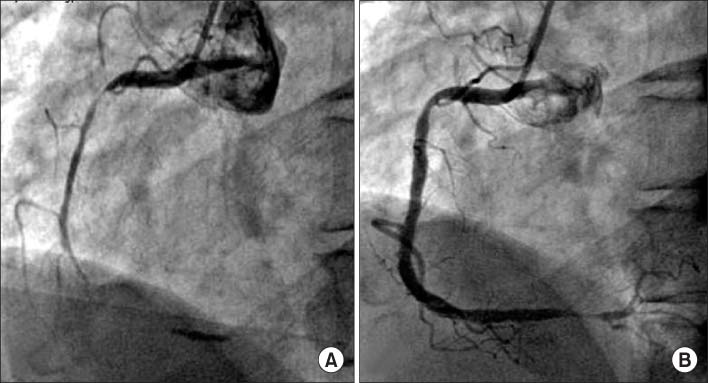

Fig. 3

Coronary angiogram. (A) Coronary angiogram reveals a severe spasm in the proximal and distal portion of right coronary artery. (B) The proximal and distal spasms of the right coronary artery are improved by repeated intracoronary injection of nitroglycerine.

Fig. 3 Coronary angiogram. (A) Coronary angiogram reveals a severe spasm in the proximal and distal portion of right coronary artery. (B) The proximal and distal spasms of the right coronary artery are improved by repeated intracoronary injection of nitroglycerine.